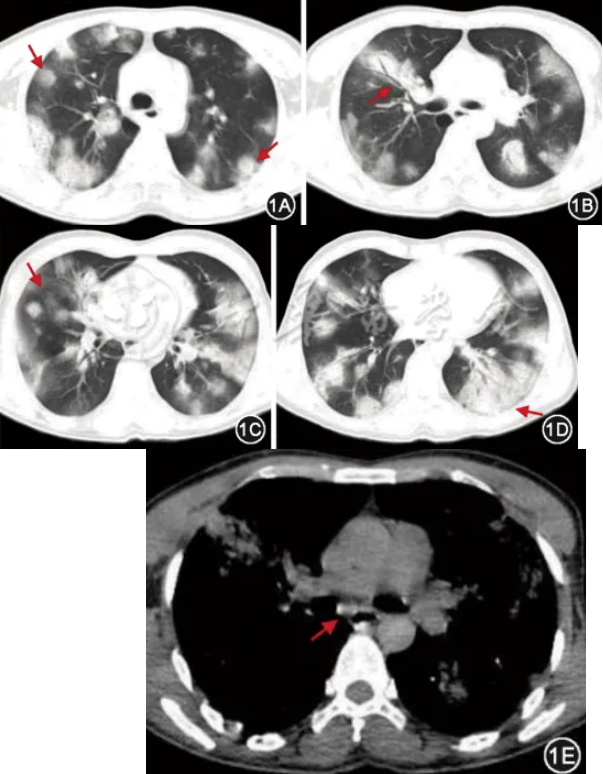

入院第4天,BALF的靶向高通量测序(targeted high-throughput sequencing,tNGS)回报病原体仅为贝纳柯克斯体,均一化序列数为85,微生物估测浓度为5.6×10^6/L,患者病情好转,撤离呼吸机成功,停用利奈唑胺、甲泼尼龙及左氧氟沙星,将亚胺培南降级为哌拉西林他唑巴坦(4.5 g,3次/d)静脉滴注,加用多西环素(100 mg,2次/d)口服,并转入普通病房。入院第10天好转出院,继续多西环素治疗15 d。出院后1个月复查胸部CT可见双肺渗出明显好转(图3)。

图3 2024年4月25日胸部CT可见双肺渗出性病变明显吸收,双肺散在磨玻璃影(图3A~3D),7组淋巴结减小,短径7.8 mm(图3E,箭头)